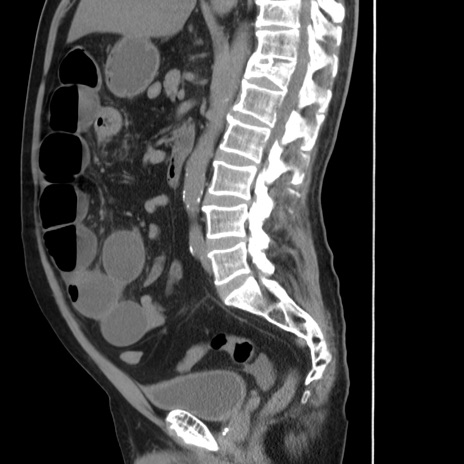

症例20(矢状断像)

【症例】 60歳代男性

【主訴】 腹部膨満、嘔吐

【現病歴】5日前頃より倦怠感を認め食事量減少し4日前の朝嘔吐、食事摂取困難となった。 3日前近医受診し点滴施行され整腸剤などを処方された。 当日他院を受診し、腹部膨満著明、炎症反応の上昇(CRP10.8、WBC11200)あり、紹介受診となる。

【身体所見】 意識JCS1 受け答えがはっきりしないBP 111/57mHg、 P 67bpm、、BT35.2°C、SpO2 97%(RA)、 腹部:膨隆、打診で鼓音あり、全体的に圧痛有り、腸蠕動音(-)、反跳痛ははっきりせず。

【データ】WBC 11400、CRP 14.20